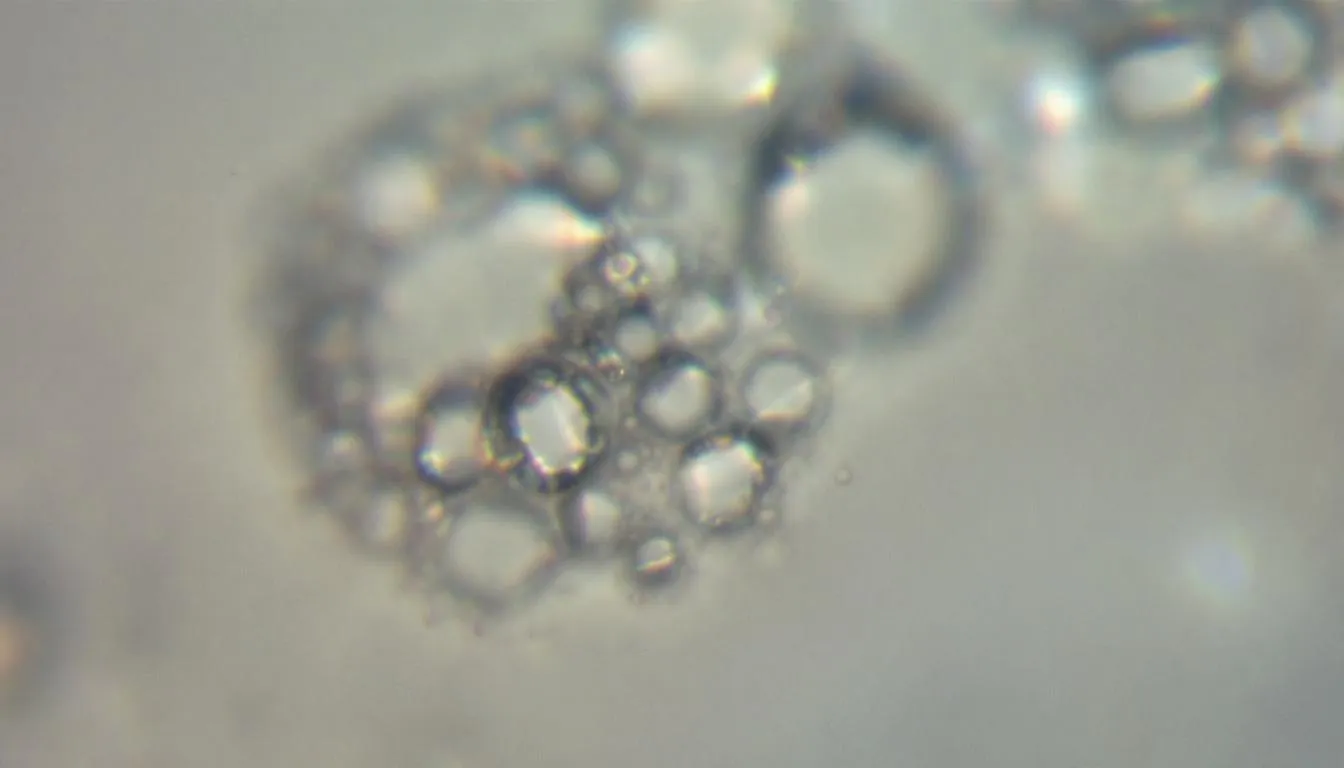

L’équipe de chercheurs a mené des expériences in vitro, c’est-à-dire en laboratoire sur des cultures de cellules cancéreuses ovariennes. Leurs découvertes sont particulièrement encourageantes. Ils ont observé que le CBD et le THC parvenaient à tuer les cellules cancéreuses et à freiner les marqueurs de la croissance tumorale.